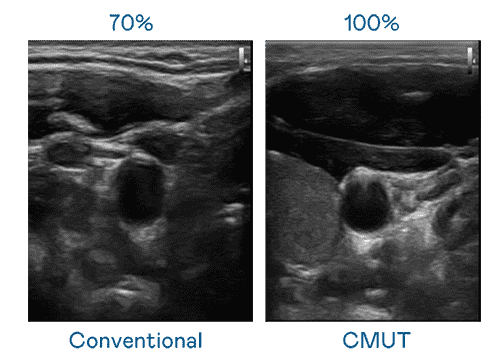

CMUT 技术是一种用电容式微机电元件来产生超音波讯号的技术。。。。与传统 PZT 压电式技术相比,,,CMUT 频宽增加 30%,,更宽频的超音波讯号让影像解析度大幅提升,,,,是实现高影像品质医疗超音波扫描、、、促进精准医疗发展的关键技术。。。。

大频宽带来超清晰影像

超音波影像的解析度高低,,,,首先取决于探头能发出的讯号频宽。。。CG电子 CMUT 可提供高清晰的超音波讯号,,提供高频宽、、、高灵敏度、、、影像纹理细节更高的超音波影像,,,协助医护人员缩短影像判读时间及利用精准的医疗影像进行诊断。。。